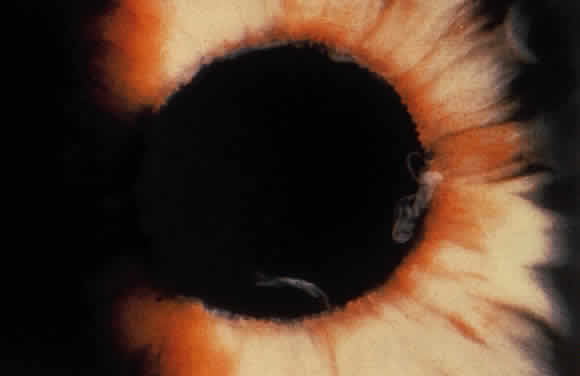

Exfoliative material frequently is observed at the pupillary border (Fig. 4) and should suggest the diagnosis of exfoliation even before the pupil is dilated.27 In addition, defects of the pigmented pupillary ruff are commonly seen. Aasved reports pupillary defects in 6.1% of eyes without XFS and in 74% of eyes with XFS.50 He further notes that in patients with unilateral XFS, pupillary ruff defects were twice as common in the affected eyes when compared with the fellow eyes. Iris transillumination defects in a moth-eaten pattern often are observed. Although these generally are limited to the region of the sphincter (Fig. 5), several patients also have diffuse midperipheral defects.51